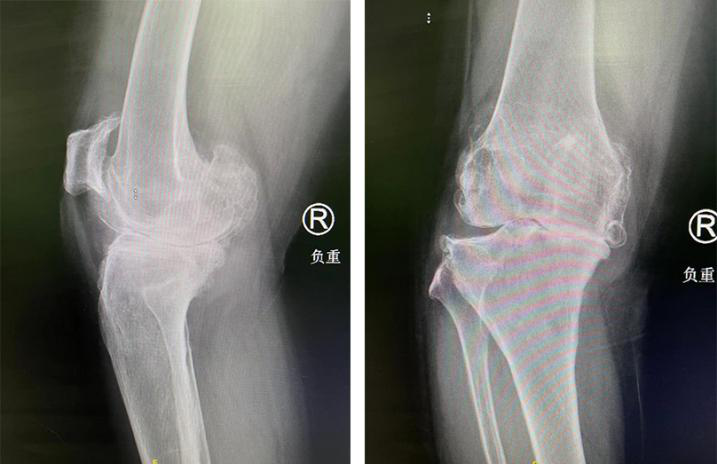

术前

原来,张大姐在20年前双膝关节莫名出现疼痛,尤其是在累了之后,疼痛更是加剧。当时,忙于事业打拼的张大姐觉得这是劳累所致,自己休息休息应该就没事了,所以没放在心上,但随着时间的流逝,双膝关节的疼痛逐渐加重,更是出现关节肿胀、内翻畸形以及活动受限等症状。

这下,可让张大姐警觉起来,开始吃药、打针、按摩等等治疗,起初还有效果,但时间久了又开始复发。直到5年前,张大姐的右膝关节症状加重,出现夜间休息时僵硬的情况,活动范围明显缩小,只能在室内进行活动。即使这样,张大姐的右膝关节有时候疼起来,就连吃镇痛药也无法缓解……

入院后,关节外科郝亮医生为张大姐进行了系统检查,行X线检查提示双膝关节骨关节病。“对于比较严重的膝关节骨性关节炎,尤其是这类经保守治疗后无改善的患者,人工全膝关节置换手术是当下较为针对性的一种治疗方法——用人工关节部件替代损坏的关节,矫正肢体力线,消除膝关节疼痛,维持关节稳定性,从而达到恢复膝关节功能的目的。”郝亮医生介绍道。

随后,郝亮、蒋涛、朱信飞手术团队为张大姐进行了智能导航下右侧人工全膝关节置换术。术中,在智能导航的规划下,精确定位力线位置,辅助手术医生进行截骨及假体安放,最终仅用时1.5小时便完成手术。经测量,患者下肢力线从术前的内翻25°、屈曲畸形10°,至术后内翻0°、膝伸直可达0°、膝关节屈曲至达120°,改善明显。